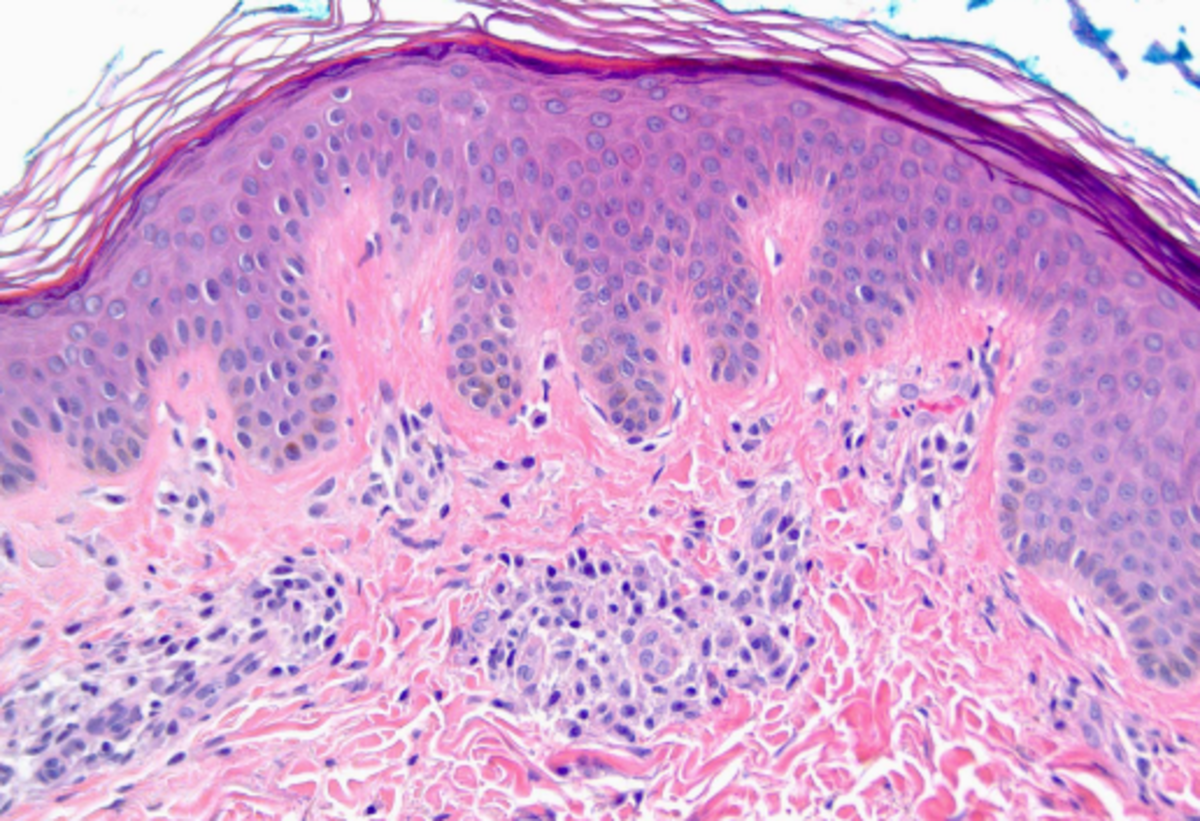

Στην προχωρημένη Συστηματική Μαστοκυττάρωση, η ανεξέλεγκτη ανάπτυξη νεοπλασματικών μαστοκυττάρων προκαλεί οργανικές βλάβες (π.χ. ηπατική δυσλειτουργία), χαμηλό αριθμό αιμοσφαιρίων και απώλεια βάρους. Οι πάσχοντες από τη νόσο, πάσχουν επίσης από εξουθενωτικά συστημικά συμπτώματα όπως κνησμός (σοβαρή φαγούρα στο δέρμα) που προκαλείται από την απελευθέρωση φλεγμονωδών μεσολαβητών από τα μαστοκύτταρα, όπως ισταμίνη, στο αίμα.

Ο ανεξέλεγκτος πολλαπλασιασμός των μαστοκυττάρων προκαλείται σε πολλούς ανθρώπους από μια μετάλλαξη του γονιδίου ΚΙΤ – η συνηθέστερη μετάλλαξη, κωδικοποίησης της υποκατάστασης D816V, εμφανίζεται κατά προσέγγιση στο 90% των ασθενών. Η μετάλλαξη του γονιδίου KIT καταλήγει στην ενεργοποίηση του ενζύμου KIT, το οποίο πυροδοτεί τον μη φυσιολογικό πολλαπλασιασμό και την επιβίωση των μαστοκυττάρων.